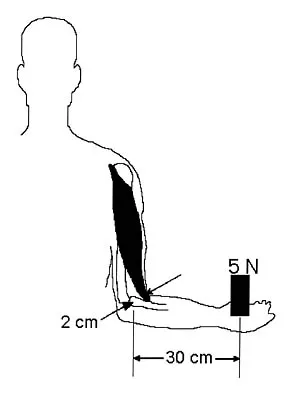

Question 25

During a posterior approach to the right Achilles tendon, the surgeon encounters a nerve running with the small saphenous vein as shown in Figure 22. This nerve innervates what part of the foot?